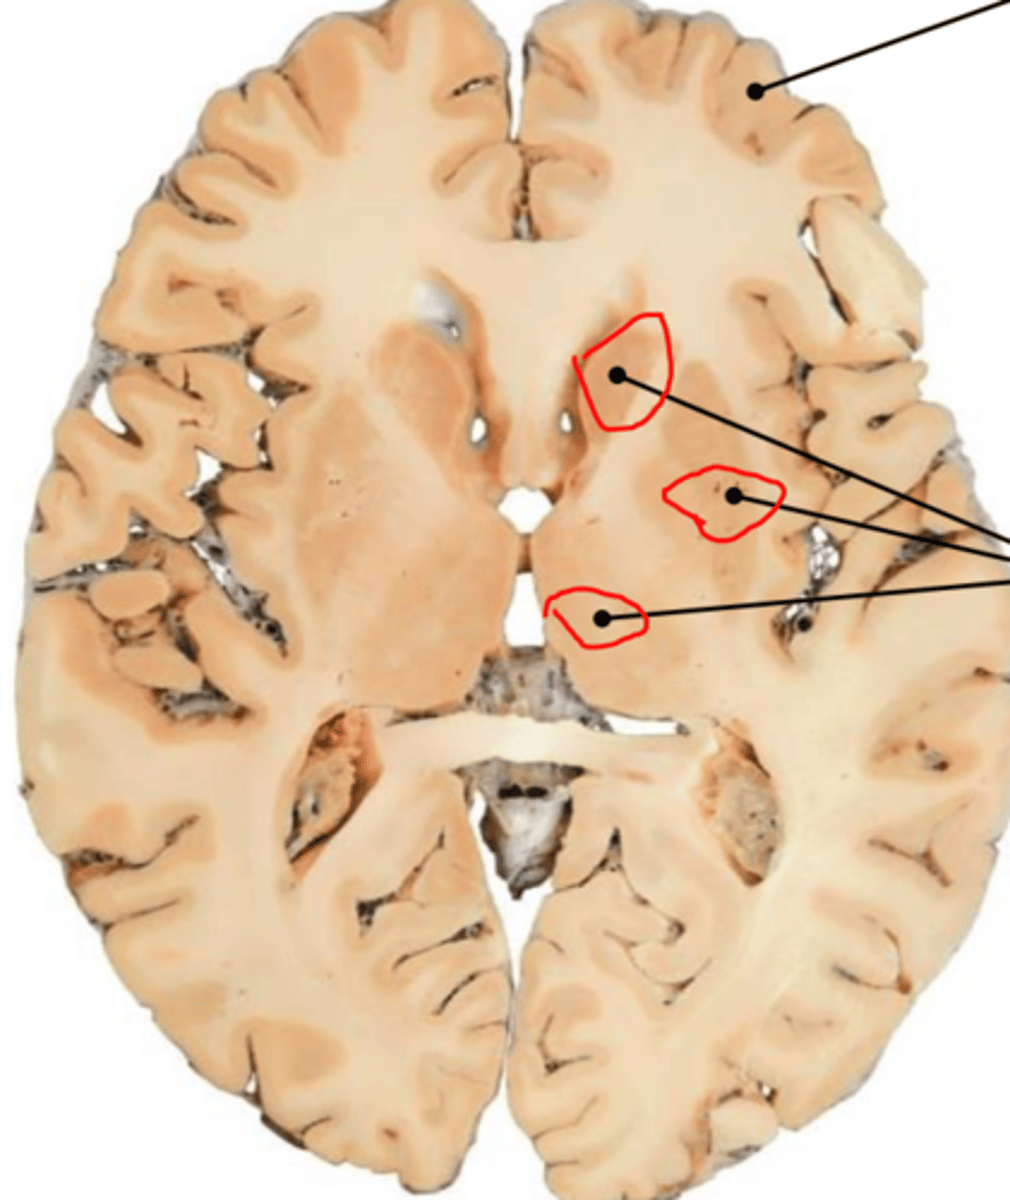

cerebrum, and deeper grey matter (thalamus, hypothalamus, and basal nuclei)

white and grey matter

myelinated axons

cell bodies

thalamus, hypothalamus and basal nuclei

what is the basal nuceli

collection of cell bodies, pass voluntary motor signals from cerebrum to other areas of brain and spinal cord